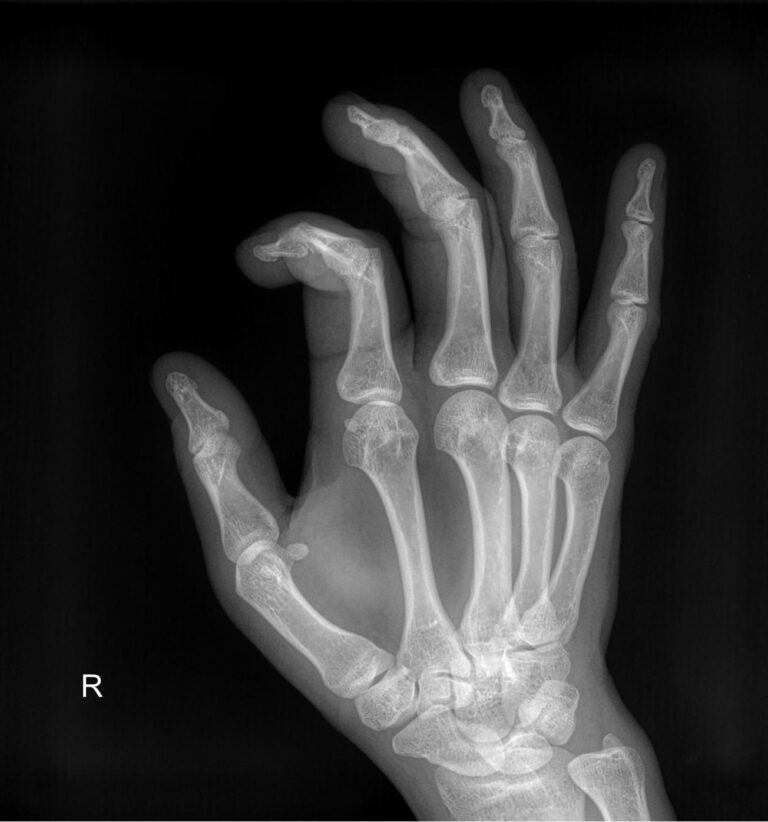

Ладонь и пальцы ― один из самых сложных участков в организме человека. Здесь сосредоточено огромное количество мелких суставов, каждый их которых может воспалиться или быть поврежденным в результате профессиональной деятельности и спорта. Изменения, связанные с возрастом или хроническим заболеванием, также влияют на состояние и функции кистей рук.

Болезни кистей серьезно ухудшают качество жизни, поэтому такие патологии редко игнорируют. Однако их симптомы схожи, что требует тщательной диагностики перед тем, как выбрать метод лечения. Одно из базовых исследований ― рентгенологическое. Это простое, быстрое, информативное и недорогое исследование. Современное цифровое оборудование, которое используют в клинике «Доступная медицина», во время процедуры несет минимальную дозу облучения. Это делает рентген практически безопасным методом обследования.

Что показывает рентген кисти

В протоколе рентгенолог описывает изменения, которые произошли в области исследования:

• Состояние суставных щелей;

• Соответствие друг другу суставных поверхностей;

• Патологические изменения поверхности суставов;

• Состояние костной ткани ― травматические и дегенеративные деформации;

• Возможные новообразования;

• Мягкие ткани.